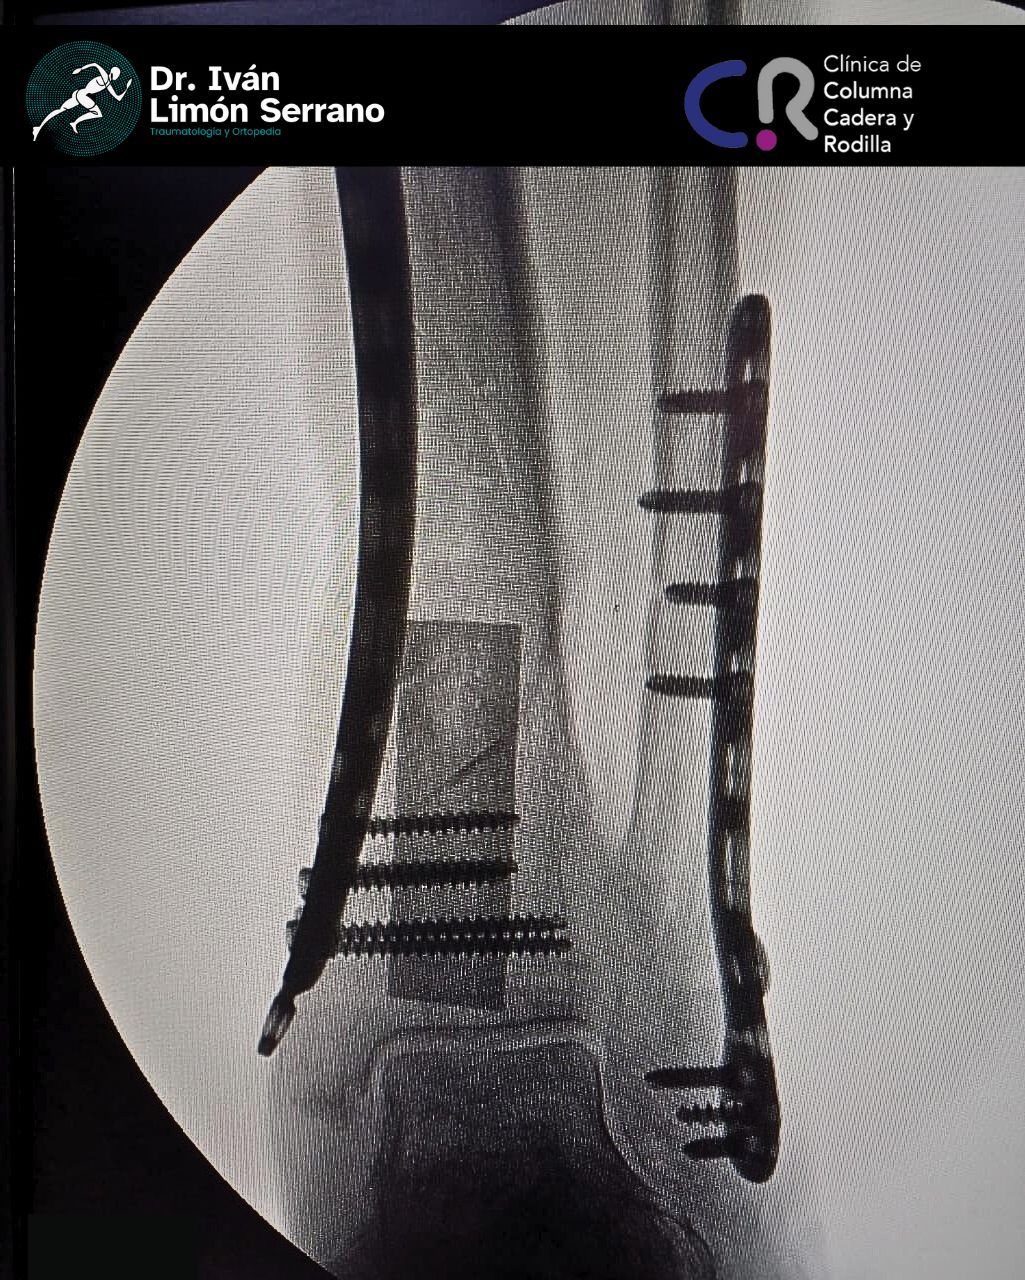

Duda sobre Fractura de tobillo y pie

Hola, en septiembre cumpliré 5 años de una cirugía de tibia y peroné pero hace como 4 días comencé con molestias donde traigo una placa y algunos tornillos, siento punzadas cerca de donde tengo los tornillos además de hinchazón en el pie, ¿a que se deberán estos malestares?

Se puede hacer el retiro de la placa, te recomiendo tomar nuevas radiografías y acudir con un ortopedista.

Dr. Iván Limón Serrano